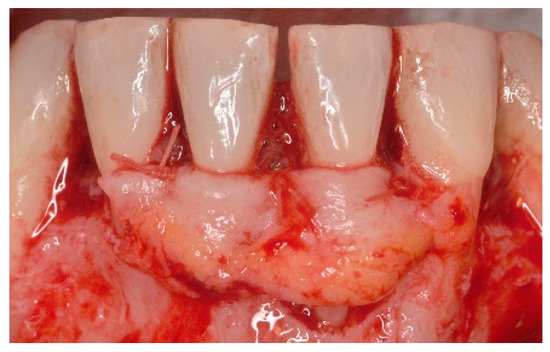

5. Materials and Methods

6. Results